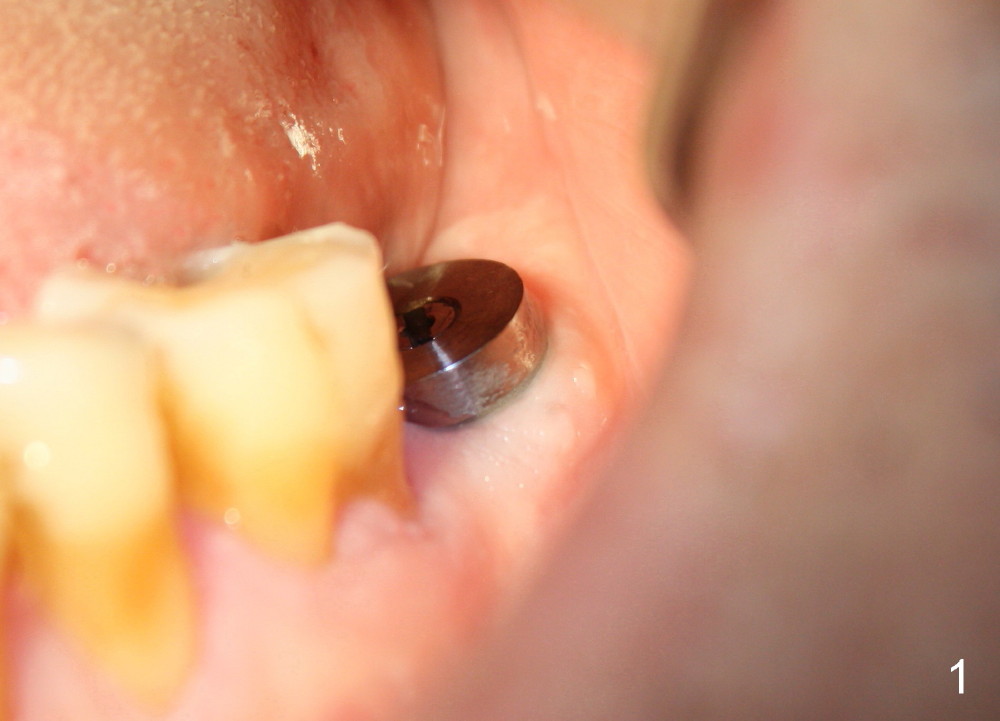

The soft tissue heals around the implant 1 months postop (Fig.1), but the implant (7x11 mm) is unstable. It should have been placed 2 mm deeper (Fig.2).  It is splinted for the neighboring tooth (Fig.3).  When the splint is removed 4 months later, the implant remains mobile.  It is removed with infiltration anesthesia.  The osteotomy is deepened by approximately 2 mm.  A 7x14 mm tap is inserted with stability (Fig.4); there is apical space to be engaged further (arrowheads).  A 7x14 mm implant is placed with insertion torque > 60 Ncm (Fig.5 I); an abutment (A) placed to keep perio dressing in place.